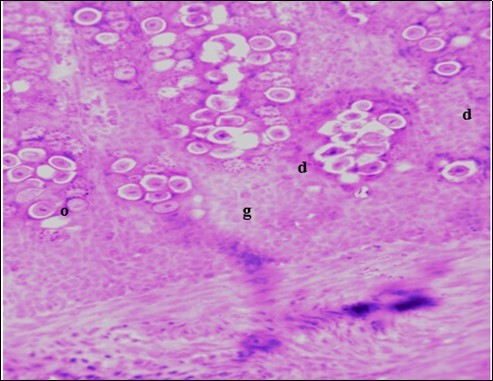

In this study, the reduction in oocyst count observed in the treated group was compared with amprolium could be attributed to the presence of a bioactive compounds azadiractin A which is known to bind membrane cholesterol, altering the integrity of the parasite membrane, resulting in loss of homeostasis and eventual death of the parasite 29]. Also, limonoids contained in NeemAzal® inhibit protein digestion and uptake of vitamins and minerals by the parasites in the gut 17. This action results in impaired nutrient utilization, reduced growth, and multiplication of the parasite which could contribute to the reduced oocyst count observed. Extracts of neem and mahogany when used individually have been reported to reduce oocyst count in avian coccidiosis 11,12. The observed reduction in oocyst count and the significant increase in weight gain of the birds when treated with NeemAzal®, as compared with the negative control group could probably be due to the inhibition of inflammation in the intestinal mucosa which is suggestive of an increased nutrient absorption across the intestinal wall and enhanced feed conversion ratio compared to the negative control this is in agreement with reports by Nwosu et al.12 and Biu et al.11 who also reported an increased weight gain and feed conversion ratio in birds treated with only Khaya senegalensis extracts and Azardiractaindica, respectively. The observed increase in RBC and haemoglobin concentration is indicative of the erythropoieticability of the NeemAzal®, which is beneficial since the Eimeria parasite in the epithelia of the intestines causes bloody diarrhoea and consequently anaemia (Table 1). This finding is in consonance with 15 who reported an anti-anaemic effect of Khaya Senegalensis on phenyl hydrazine-induced anaemia in rats. Neem has been shown to possess anti-anaemic properties in rats 14. The significant increase in mean weight gain in treated birds when compared to the negative control is possibly due to the inhibition of inflammation in the intestinal mucosa which is suggestive of an increased nutrient absorption across the intestinal wall and enhanced feed conversion ratio compared to the negative control. Nwosu et al.12 and Biu et al.11 reported an increased weight gain and feed conversion ratio in birds treated with only Khaya Senegalensis andAzadiractaindica extracts, respectively. In a similar study, Neem acts like toltrazuril exhibiting anticoccidial. In addition, exposure of broiler chickens to 20000 Oocysts of Eimeria tenellacaused generalized degeneration of the caecal glands with massive Oocysts and gametocyts within the caecal glands with fibrosis (Figure 3, Figure 4 & Figure 5), however, broiler chickens treated with NeemAzal® post exposure to 20000 Oocysts of Eimeria tenella, shows equal numbers of caecal tissues with non-observable histopathological lesions (Figure 4), possibly due to the antioxidant and anti-coccidian effects of NeemAzal®. The exact mechanism of action of neem against coccidian parasites is unknown, but a report by the National Research Council 1992 30, suggested that aqueous neem leaf extract, when taken orally, produces an increase in red cells, white blood cells and lymphocyte counts thus enhancing the cellular immune response, increasing antibody production and so most pathogens can be removed before they cause the symptoms associated with disease this was in agreement with this study as seen in Table a remarkable increase of the RBCs.

Figure 4.Photomicrograph of caecum of chick administered 20000 Oocysts of Eimeria tenella and untreated showing generalized degeneration of the caecal glands (d) with massive Ocysts (o) and gametocytes (g) largely within the caecal glands X250 (H&E).

In addition, the generalized degeneration of the caecal glands, moderate numbers of gametocytes within the glandular regions with fibrosis which underscores reparative process in response to injury evoked by coccidiosis in the chicks which was perhaps brought about by the antioxidant and chemotherapeutic effect of NeemAzal®. The observed increase in RBC and hemoglobin concentration (Table 1) is indicative of the erythropoieticability of NeemAzal®, which is beneficial since the Eimeria parasite in the epithelia of the intestines causes bloody diarrhea and consequently anaemia. This finding is in consonance with 15 who reported an anti-anaemic effect of Khaya senegalensis on phenyl hydrazine-induced anaemia in rats. If the results of this study are juxtaposed with the results of the previous studies on potent antioxidant, hepatoprotective and mitigative role of methanolic extracts of Azadirachtaindica,in both natural and experimental infection with Eimeria species and can be deduced that, NeemAzal® could be said to be a potent antioxidant, chemotherapeutic and tissue protective agent. This study also answered a question on further study advocated to determine the maximum safe levels of neem supplementation because the higher doses, due to its bitterness, may show adverse effects on feed intake which will change the performance parameters of birds (Figure 6 and Figure 7) . Light microscopic inspection of hematoxylin and eosin-stained sections revealed that the epithelial cells of the Cecum were infected by E. tenella(Figure 3 and Figure 4). The results of the safety study showed that exposure of chickens to NeemAzal® at 200mg/kg body weight did not alter the histoarchitecture of liver and kidney (Figure 6 & Figure 7) which is similar to the work conducted in the same environment by a group of Scientists 34. It is therefore recommended that NeemAzal® could be used as a coccidiostat to replace the expensive anti-coccidiostats in the market.